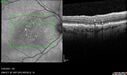

80 year old female. Dry AMD with GA in the left eye and pigment migration visible on OCT scan.

VA 20/40 OD, 20/160 OS